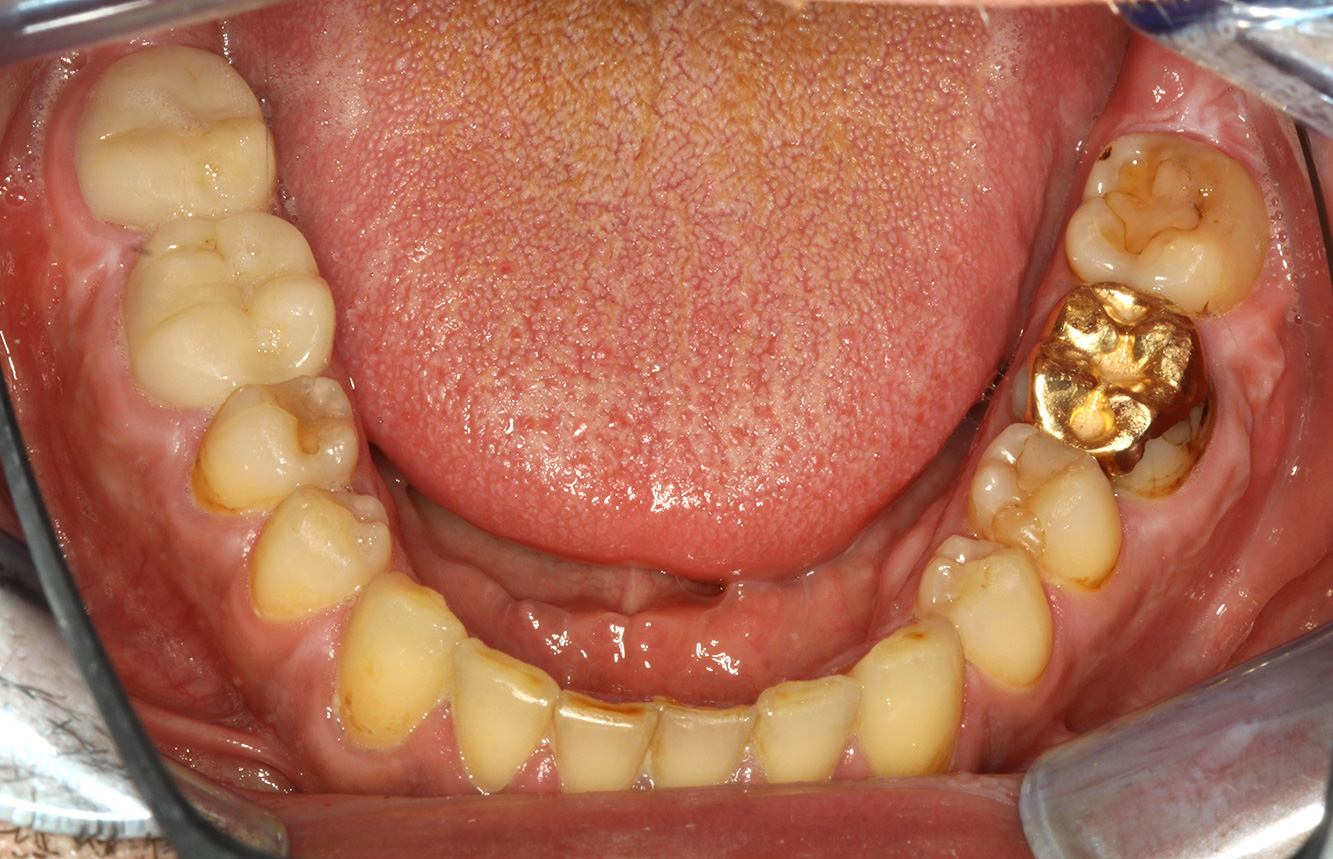

The healthy patient with pre-existing periodontal disease & peri-implantitis

A 52-year-old patient presents at a preventive care session. The patient has no systemic disease and is not taking any medication. He has had various dental treatments and also has two active carious lesions. In addition, the patient has four implants (2nd, 3rd and 4th quadrants). He is revealed to have early periodontal disease (stage IV, grade B). His periodontal condition is stable; a probing depth of Probing depths (ST) of 5 mm is only evident at the implant in region 36. Gingivitis is also identified. more